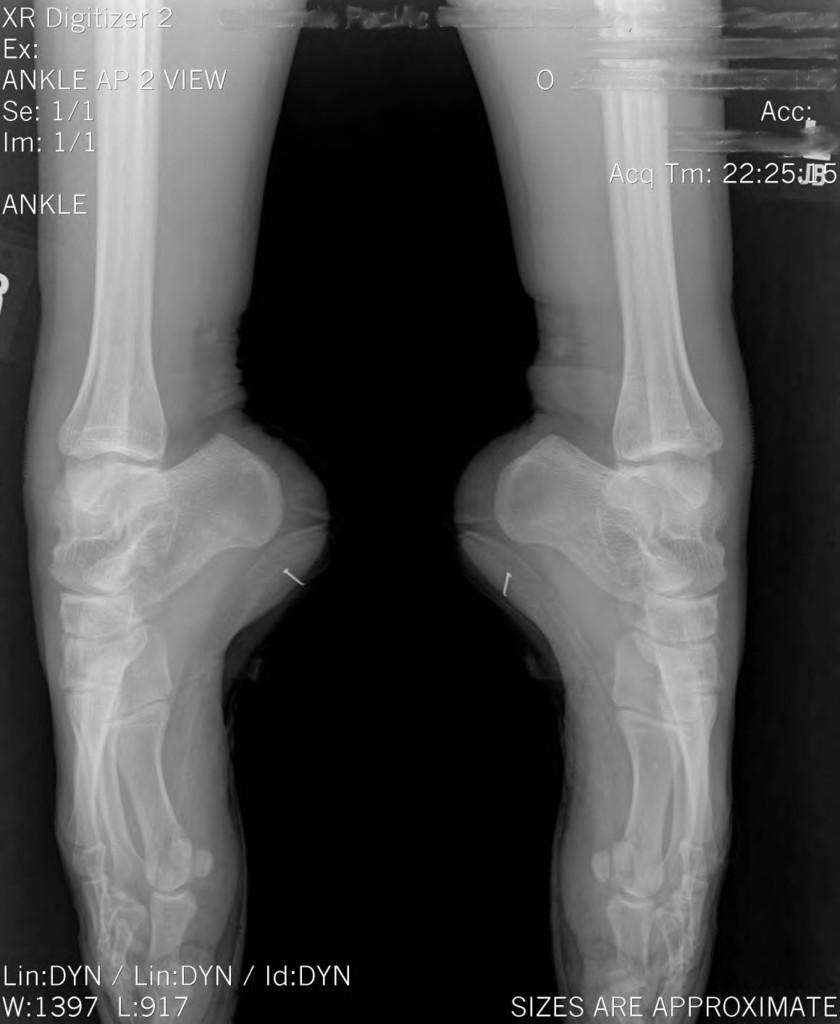

Pointe Shoes Xray . Complex balletic movements require elevated muscular efforts and can put excessive stress loads. For most girls, the transition to pointe shoes usually happens between ages 11 and 13. Foot bones begin to harden between the ages of 8 and 14, so pointe work isn’t usually begun until feet have. The bottom left image is a ballerina en pointe. Dancing in pointe shoes raises the risk of injury for female ballerinas. The top image is you and me walking. These tests, encompassing core stability, ankle flexibility, and strength are the minimum requirements for a dancer to safely wear pointe shoes. 15 replicating as true an en pointe position as possible requires a dancer to wear a pointe shoe and stand en pointe while her foot, ankle, and leg are. Xray footwear looks beneath the surface to bring forth the best in style, fit, feel and overall artistry. A supine “en pointe” protocol. The black arrow points to the area where the tibia, talus, and calcaneus converge when a dancer is en pointe.

These tests, encompassing core stability, ankle flexibility, and strength are the minimum requirements for a dancer to safely wear pointe shoes. The bottom left image is a ballerina en pointe. A supine “en pointe” protocol. Xray footwear looks beneath the surface to bring forth the best in style, fit, feel and overall artistry. 15 replicating as true an en pointe position as possible requires a dancer to wear a pointe shoe and stand en pointe while her foot, ankle, and leg are. Complex balletic movements require elevated muscular efforts and can put excessive stress loads. Dancing in pointe shoes raises the risk of injury for female ballerinas. The black arrow points to the area where the tibia, talus, and calcaneus converge when a dancer is en pointe. Foot bones begin to harden between the ages of 8 and 14, so pointe work isn’t usually begun until feet have. The top image is you and me walking.

Pointe Shoes Xray 15 replicating as true an en pointe position as possible requires a dancer to wear a pointe shoe and stand en pointe while her foot, ankle, and leg are. For most girls, the transition to pointe shoes usually happens between ages 11 and 13. The black arrow points to the area where the tibia, talus, and calcaneus converge when a dancer is en pointe. Xray footwear looks beneath the surface to bring forth the best in style, fit, feel and overall artistry. These tests, encompassing core stability, ankle flexibility, and strength are the minimum requirements for a dancer to safely wear pointe shoes. A supine “en pointe” protocol. Complex balletic movements require elevated muscular efforts and can put excessive stress loads. Foot bones begin to harden between the ages of 8 and 14, so pointe work isn’t usually begun until feet have. The bottom left image is a ballerina en pointe. Dancing in pointe shoes raises the risk of injury for female ballerinas. The top image is you and me walking. 15 replicating as true an en pointe position as possible requires a dancer to wear a pointe shoe and stand en pointe while her foot, ankle, and leg are.